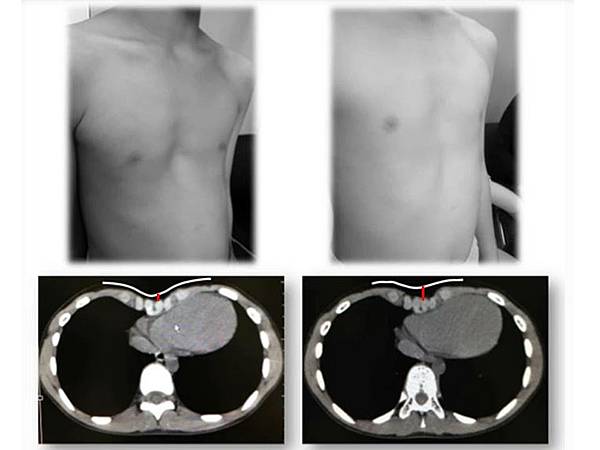

病例三,

25

歲男性